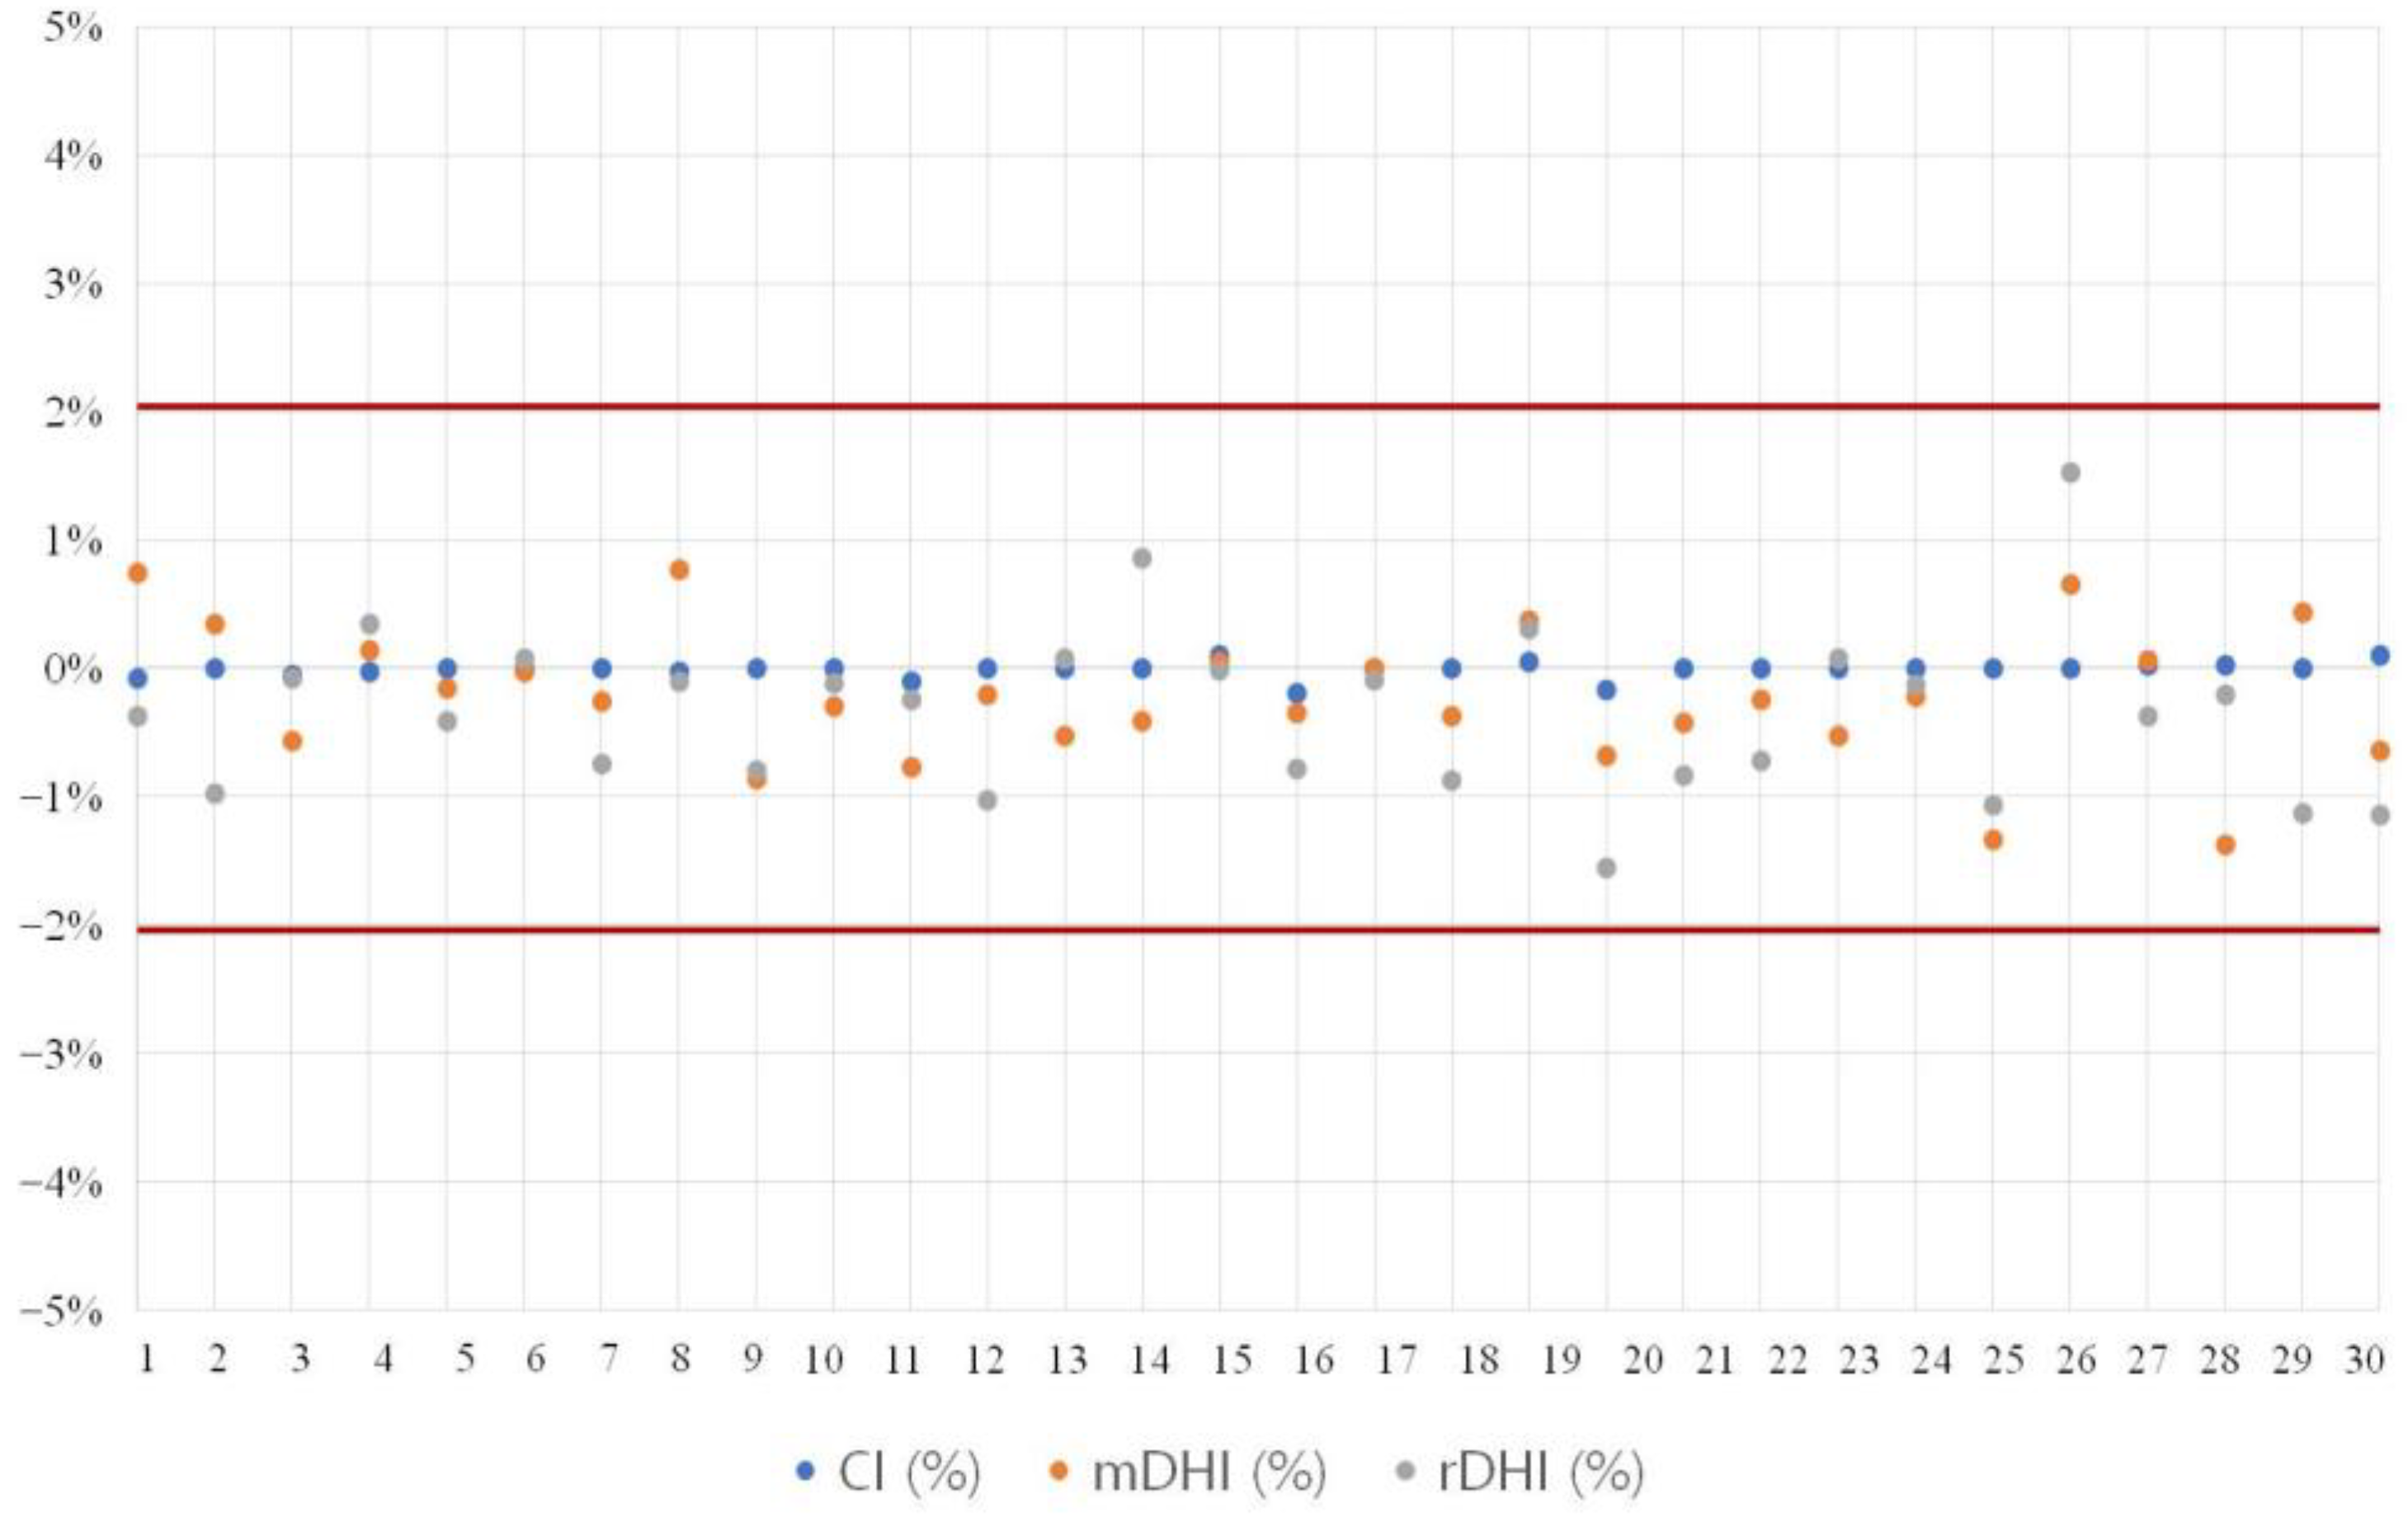

2.5. Evaluation of Treatment Plan Consistency

3.2. Evaluation of Treatment Plan Consistency